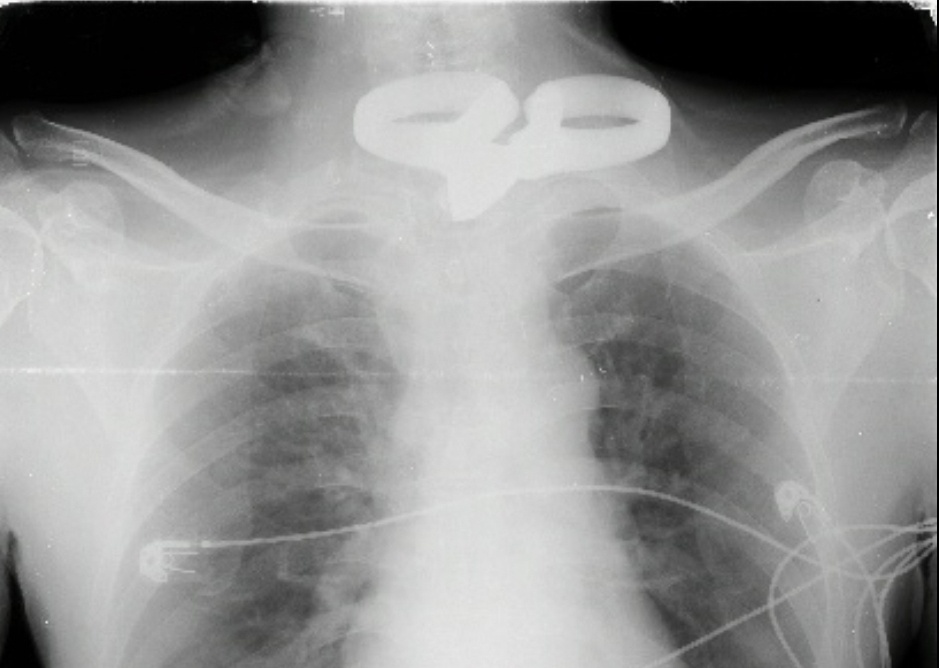

| Hình dị vật trên phim Xquang |

Trước đó, nam bệnh nhân L.V.H (SN 1980, ngụ tỉnh Sóc Trăng) được chuyển đến BVĐKTƯ Cần Thơ lúc 14h ngày 19/2 trong tình trạng vết thương vùng hõm ức, dị vật là chiếc kéo sắt dài 24 cm; vết thương thấu bụng 2cm; tiền sử hai mắt bệnh nhân không còn thị lực 10 năm.

Kết quả X-Quang, chụp cắt lớp vi tính ghi nhận chiếc kéo xuyên giữa cột sống ngực D1. Bệnh nhân được chỉ định phẫu thuật cấp cứu lấy dị vật và thám sát vết thương tủy sống. Các BS nội soi thực quản thấy không tổn thương dọc theo ống thực quản qua vị trí kéo đâm xuyên từ trước vào thân sống ngực.